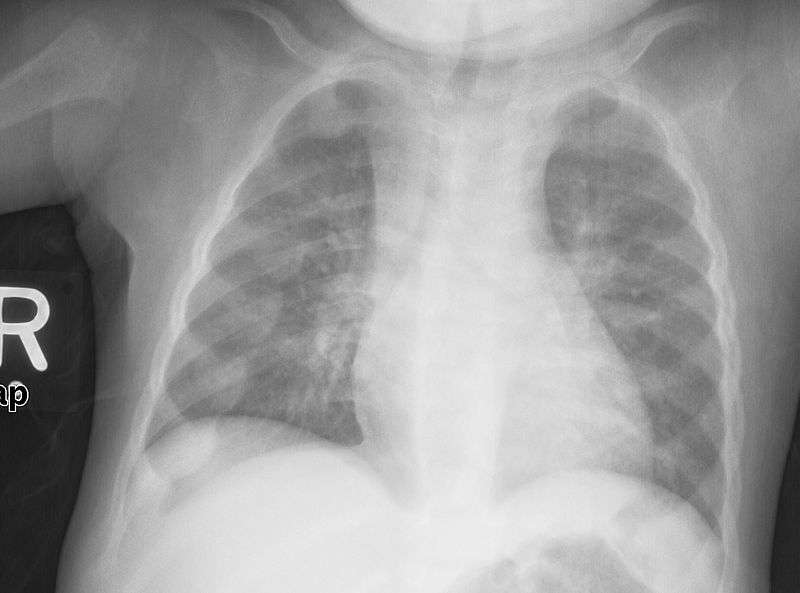

Common features of rickets include:

- Pigeon breast deformity

- Rachitic rosary chest

Rickets is pathognomonic associated with “pigeon-breast deformity” on chest X-ray

The pigeon chest deformity is the inward bending of the ribs with anterior protrusion of the sternum.

Rachitic rosary in children is caused by osteoid deposition at the costochondral junction.